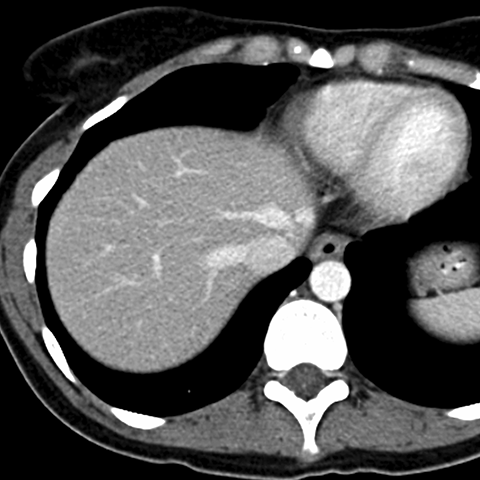

Normal Liver, CT ( axial ) [1 of 9]